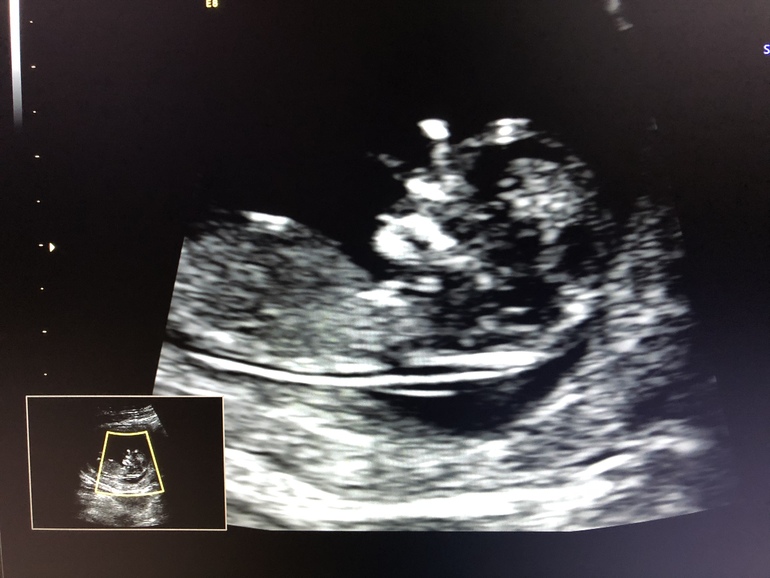

Результаты: УЗИ, КТГ, доплера, скринингаСегодня у меня был долгожданный первый скрининг. По УЗИ все показатели в норме, правда пришлось УЗИ делать два раза, малыш крепко спал и не собирался врачу помочь измерить некоторые важные показатели, я и на левом и на правом боку полежала и покашляла, а ему ничего, свои биологические часы. Отправили выпить чай и скушать конфетку и со второго раза всё сразу увидели. Теперь 7-10 дней буду ждать показатели крови. И самое важное сказали будет мальчик, муж сегодня самый счастливый человек на планете, он так ждёт сына 😍😇

Мне полностью малыша не показали, в конце дали сфотографировать только этот снимок, когда меряли ТВП.